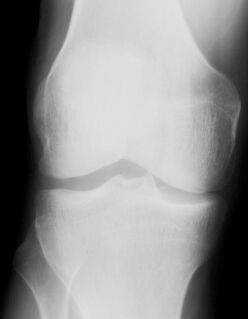

Стандартные проекции, применяемые при рентгенографии коленного сустава - прямая (передне-задняя) и боковая (рис.1). По мере необходимости их дополняют правой или левой косой, а также аксиальной проекциями. Основным правилом при рентгенологическом исследовании коленного сустава является полипозиционность.

Рисунок 1. Проекции, применяемые при рентгенографии коленного сустава.

Схема к рисунку 1.

1. Латеральный мыщелок бедренной кости.

2. Медиальный мыщелок бедренной кости.

3. Межмыщелковая ямка.

4. Основание надколенника.

5. Верхушка надколенника.

6. Латеральный надмыщелок бедренной кости.

7. Медиальный надмыщелок бедренной кости.

8. Латеральный мыщелок большеберцовой кости.

9. Медиальный мыщелок большеберцовой кости.

10. Межмыщелковое возвышение.

11. Головка малоберцовой кости.

12. "Пятно" Людлофа.

13. Рентгеновская суставная щель большеберцово-малоберцового сустава.

14. Суставная поверхность (трохлея) головки бедренной кости.

15. Суставная поверхность надколенника .